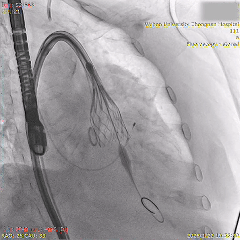

最终造影可见瓣膜形态佳、位置理想,冠脉良好,无明显瓣周漏